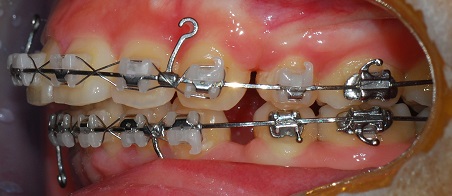

측면 사진

공간이 거의 닫혀가요 신기방기